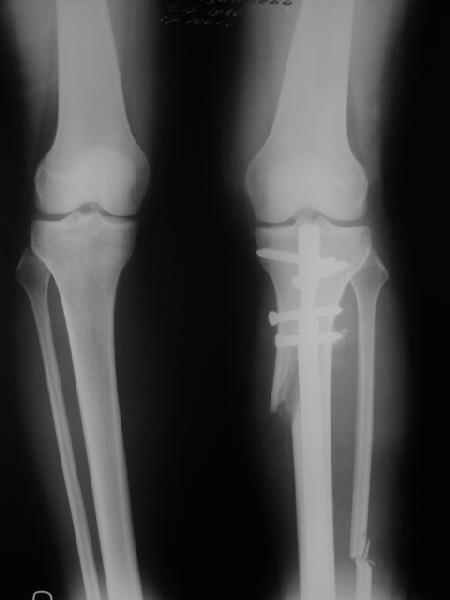

I prefer a medial opening wedge. Currently I prefer the tomofix system by synthes. Its instrumentation allows "dialing in" the correction nicely, and the fixed angle construct provides excellent stability. A few other companies have similar systems, Arthrex for example. Trying to hinge the correction on intact lateral cortex (1 cm.) is key to preserve stability.

The nonunion/hardware failure rate is substantially higher when the lateral cortex is breeched. Fibular osteotomy not required.

Attached is a screen capture from the AO foundation website which has an excellent training module on performing an opening wedge HTO. It shows from preop planning to intra-op techniques. It is helpful even if you don't use their product to perform the procedure. Certainly it is not mandatory to use any osteotomy system to obtain and secure a well done osteotomy - im not sure what instrumentation you have access to.

Yesterday one leg was done (my plan to make both in one session were cancelled because of external reasons). So much exciting and useful experience.

The osteotomy line i planned to make a bit oblique, but not so as you suggested. But at the moment of osteoclasis after corticotomy through the anterior stab wound the line became almost as you described. Now problem is how to reproduce thee line at the next leg ;-)

The prominent fragment seems to be useful for cosmetic purposes, because aesthetic guys perform medialization of the distal fragment to gain attractive curve at the medial side of the leg. Also all locking options became available - initially i planned to engage only two most

proximal 45 degree holes.

I cut the fibula because i externally rotated the distal fragment by 6-7 degrees. With only angular correction it didn't show any displacement.

Today CT for estimation of rotation was performed, results i will see only tomorrow. Rotation of the operated limb can be corrected with the second surgery. Comments/critics are welcome.